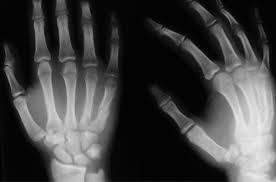

Для изучения особенностей репаративного остеогенеза при устранении деформаций различных сегментов кисти у 56 больных использовали полипозиционную рентгенографию, которую проводили после поступления больного в клинику, в процессе устранения деформации и после окончания лечения (фиксации аппаратом).

Рентгенограммы выполняли в прямой, боковой проекциях или в аксиальных плоскостях, определяя их направление, исходя из характера деформации.

У больных с неправильно срастающимися переломами при поступлении отмечалась деформация сегмента различной степени тяжести – от 5 до 40º в различных плоскостях (табл. 1, рис. 1)

В процессе устранения деформации, после корригирующей остеотомии IV-V пястных костей правой кисти и консолидации в зоне перелома, формировалась периостальная мозоль в виде муфты различной толщины. Ближе к линии перелома толщина периостальной мозоли была больше, проксимальнее и дистальнее – значительно уже (рис. 3).

Через месяц после демонтажа аппарата ось IV-пястных костей правильная, консолидация в зоне остеотомии (рис. 4).

Сохраняется периостальная реакция веретенообразной формы, объем периостальных наслоений в области IV пястной кости больше, чем в области V, что связано с неполным устранением смещения и всегда сопровождается более выраженной периостальной реакцией для ремоделирования формы кости. Границы межфрагментарного диастаза размыты, но хорошо дифференцируются (рис. 5).

У больных с неправильно консолидированным переломом на вогнутой стороне деформации также выражена периостальная реакция, хорошо дифференцируется межфрагментарный диастаз, контуры которого размыты (рис. 6).

После устранения деформации ось пястной кости или фаланги пальцев полностью была восстановлена у 49 больных. Небольшая деформация (до 5 градусов) сохранилась у семи больных с сопутствующей патологией мягких тканей. После демонтажа аппарата сохраняется периостальная реакция, умеренное разрежение в области основания и головки пястных костей.

На сравнительных рентгенограммах до и после лечения больного И., 16 лет, анатомический результат можно расценить как отличный, однако органотипическая перестройка далеко не завершена, отмечается умеренный остеопороз, размытые контуры внутреннего слоя кортикальной пластинки, очаги резорбции в местах удаленных спиц (рис. 7).